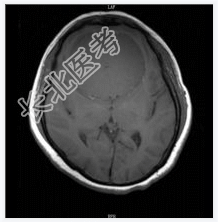

- [材料题] 患者女,55岁,视力下降数月。查体:视力下降,余神经体征阴性。

- 简答题1、诊断及依据是什么?

- 简答题2、鉴别诊断有什么?